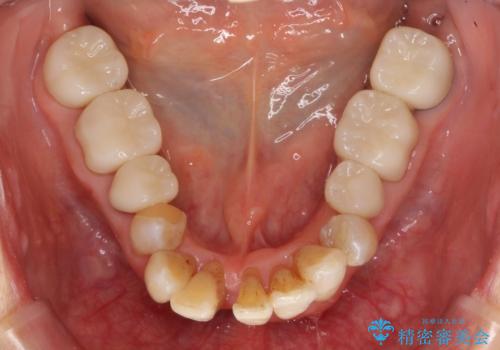

矯正治療が終わったのちに、精度の高いセラミックを装着することでより安定した噛み合わせとなり審美性も兼ね備えた口腔内状態で治療を終了し、今後のメンテナンスを行っていくことができます。